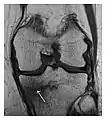

Proximal femoral fractures usually occur in osteoporotic patients, and their signs include subtle neck angulation, trabecular angulation, and subcapital impaction line. A frog-leg lateral view may be helpful if the greater trochanter is short enough. However, positioning can be difficult because of hip pain. In patients with strong suspicion of proximal femoral fracture and negative radiographs, MRI limited to coronal T1 W images and scintigraphy can be highly valuable (Figures 13 and 14). Such an option, with limited examination time, is cost-effective and allows reliable exclusion or confirmation of the diagnosis, preventing an unnecessary stay at the hospital or delayed treatment. Moreover, MRI helps to detect soft tissue abnormalities which are more frequently seen in femoral, acetabular, and pubic injuries than sacral lesions. Concomitant fractures are also frequently seen in typical pelvic sites.[1]

a

b

Figure 14: Subcapital insufficiency fracture in a 55-year-old man with a left hip pain without a history of trauma. Anteroposterior and Lauenstein view radiographs centered on the left hip do not show an obvious fracture line, but mild acetabular osteophytosis was noted consistent with hip osteoarthritis (not shown). (a) Coronal T1-weighted MRI shows a linear low-signal band through the femoral neck corresponding to a fracture line (arrowheads). (b) Bone scintigraphy shows focal uptake (arrow) corresponding to the fracture.[1]